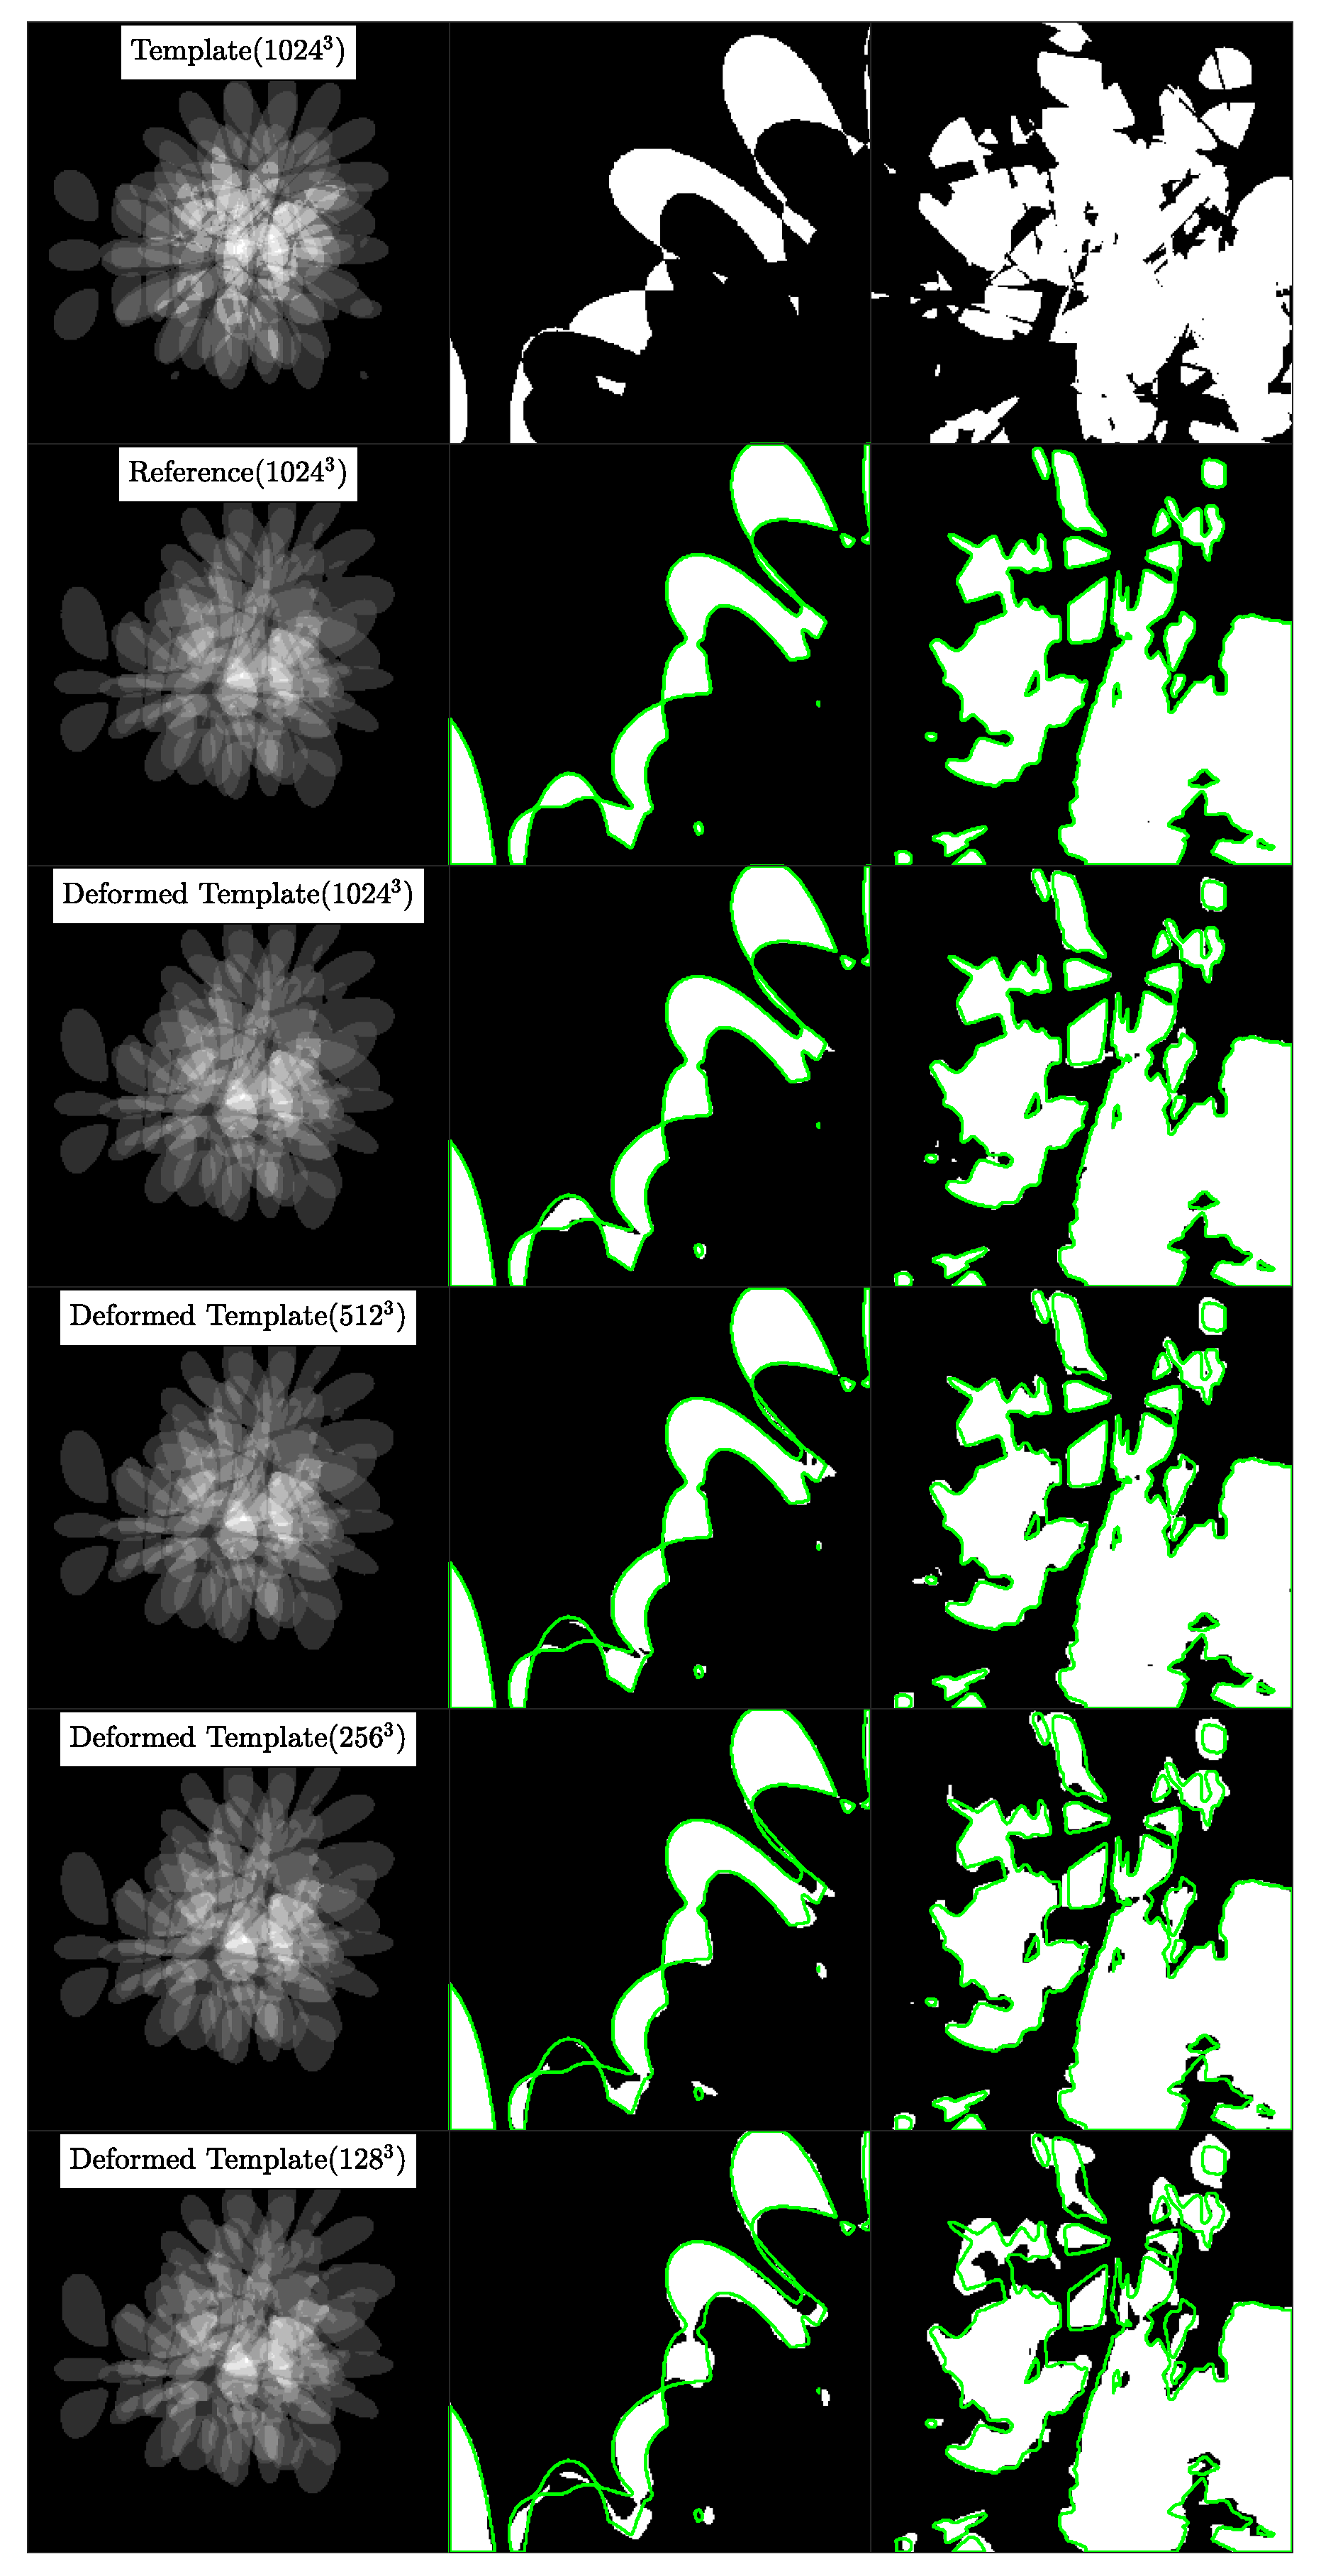

5.3. Experiment 2A: High Resolution Synthetic Data Registration

5.3.1. Dataset

5.3.2. Procedure

- We register the template image to the reference image at the base resolution n to get the velocity field . We transport using the velocity to get the deformed template image by solving Equation (3). Then, we compute the Dice score between and , which are discrete labels for and , respectively, using Equation (13).

- We downsample and using nearest neighbor interpolation to half the base resolution (for example, . Notice that we treat as a tuple. When we say , we mean ) and register the downsampled images to get the velocity . We upsample to the base resolution n using spectral prolongation and call it . We transport using by solving Equation (3) to get the deformed template image and then compute the Dice score for this new deformed template image.

- We repeat the procedure in step 2 for resolutions and and compute the corresponding Dice scores.

- changes with resolution: We use time steps for the coarsest resolution and double when we double the resolution in order to keep the CFL number fixed. All other solver parameters, except for the regularization parameters, are the same at each resolution.

- fixed with resolution: In order to study the effect of on the Dice score we keep fixed for each , instead of increasing proportionately to .

5.3.3. Results

5.3.4. Observations